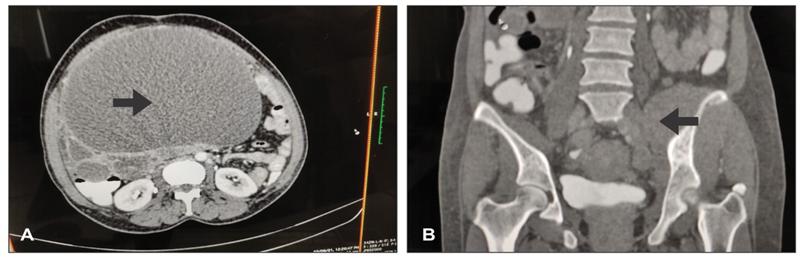

A woman aged 52 years with a history of ischemic heart disease was presented with abdominal pain and abdominal mass for the past 15 days. Per abdomen clinical examination, radiological imaging, and tumor markers were used to assess her for the same. Clinical findings suggested a smooth, mobile mass of 32 weeks in size. A computed tomography (CT) scan of the abdomen, pelvis, and thorax revealed a solid cystic mass 19 × 20 cm (right), 7 × 8 cm (left) ([Fig. 1B]), ascites with omental, muscle, and pleural infiltrates, and a lytic metastatic lesion (50 × 25 mm) at the left iliac bone ([Fig. 1A]). CA125 was 944 IU/mL, carcinoembryonic antigen was 17.3 ng/mL, and CA19-9 was 41.9 IU/mL. Due to extensive disease involving the muscle and pleura, the decision for neoadjuvant chemotherapy was made with a plan of ultrasound-guided biopsy from the lesion.

Fig. 1 (A) Cystic adnexal mass. (B) A bony lytic lesion with muscle infiltrates on computed tomography (CT) scan.